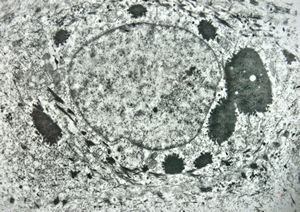

M, 11y. | mycosis fungoides v.s. - cerebriform nucleus of Sézary cell

F, 57y. | mycosis fungoides … cerebriform nucleus of Sézary cell

F, 37y. | mycosis fungoides … cerebriform nucleus of Sézary cell

M, 70y. | mycosis fungoides - Sézary cell